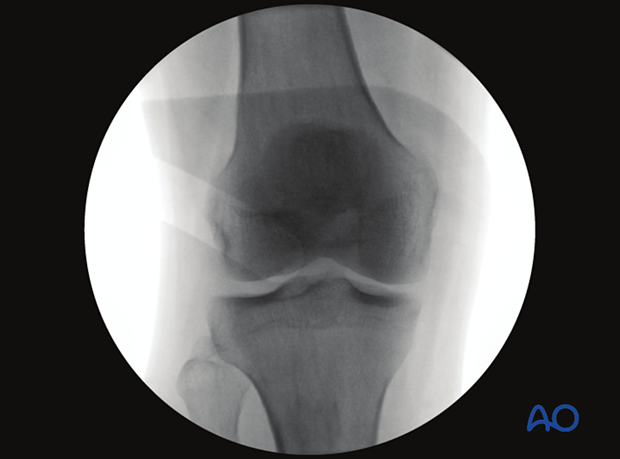

To obtain the optimal AP view of the proximal tibia:

AP images obtained with the knee in 30° flexion will not be very different from those recorded with the leg in full extension.

With the knee in 90° flexion, an AP view cannot be obtained.

The optimal AP view of the proximal tibia is obtained when:

The following lines and landmarks can be observed in the AP view of the proximal tibia:

This view is particularly useful to identify:

The correct angle between the joint line and the tibial axis (85-90°)

Images of the contralateral side may be beneficial as a reference.